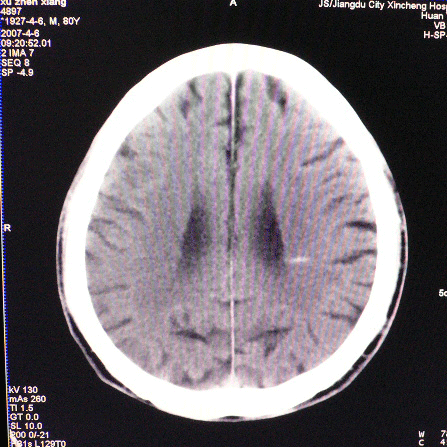

以下是引用狙击手在2007-4-8 22:45:00的发言:[br]出血?从患者的症状考虑病灶应该在左侧大脑半球的基底节区或颞顶部,如此小的病灶引起上述症状的可能性不大,患者可能有梗塞(时间短,目前ct还看不见)或是tia发作,再者像这样的线条形出血的确不多见,但还是有可能的,曾经碰到有外伤类似出血,复查后消失,所以还是慎重一点,短期复查即可。

以下是引用dyqct在2007-4-8 16:25:00的发言:[br]支持左侧放射冠区少量出血。